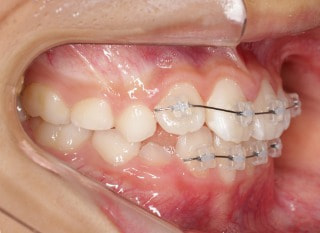

小児期第二段階

開始時

小児期の第二段階

治療中